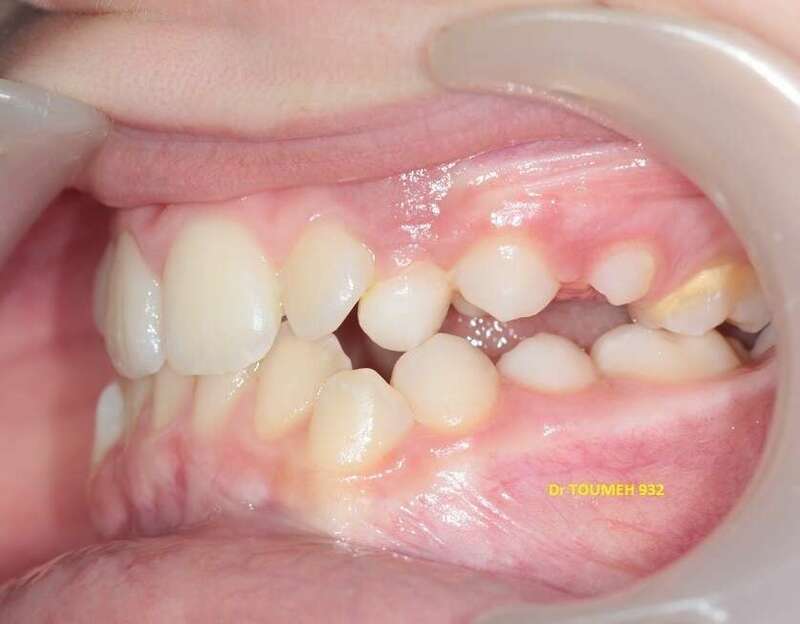

Avant

Après